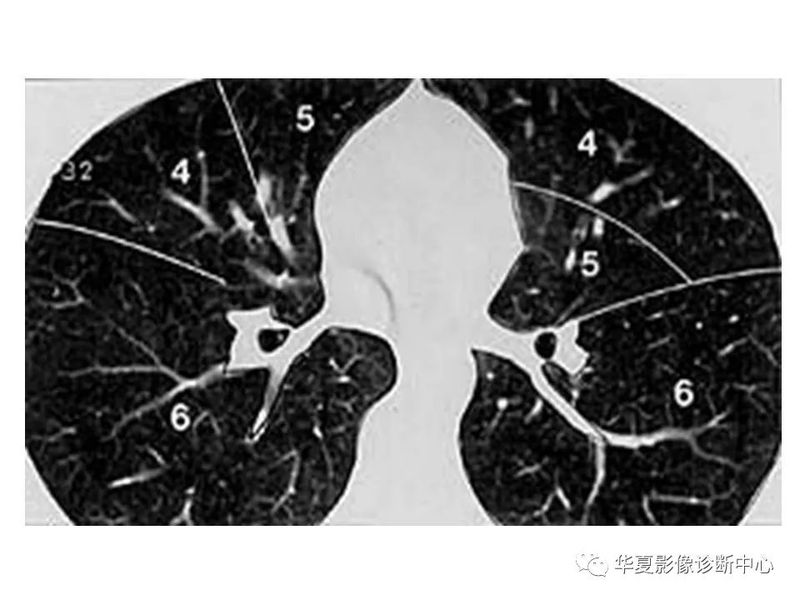

干货 | 汇总胸部CT读片扫盲知识,看懂胸部CT不再难